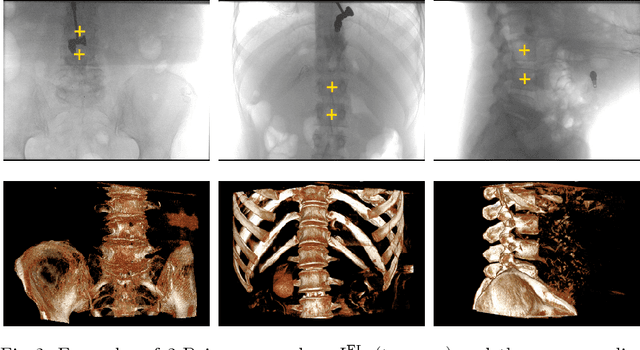

Abstract:Registration of pre-operative 3-D volumes to intra-operative 2-D X-ray images is important in minimally invasive medical procedures. Rigid registration can be performed by estimating a global rigid motion that optimizes the alignment of local correspondences. However, inaccurate correspondences challenge the registration performance. To minimize their influence, we estimate optimal weights for correspondences using PointNet. We train the network directly with the criterion to minimize the registration error. We propose an objective function which includes point-to-plane correspondence-based motion estimation and projection error computation, thereby enabling the learning of a weighting strategy that optimally fits the underlying formulation of the registration task in an end-to-end fashion. For single-vertebra registration, we achieve an accuracy of 0.74$\pm$0.26 mm and highly improved robustness. The success rate is increased from 79.3 % to 94.3 % and the capture range from 3 mm to 13 mm.